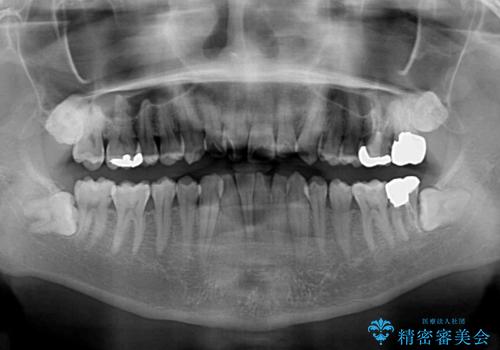

- 上下前歯の叢生を気にして来院された患者様です。

奥歯はクロスバイトとなっているので上顎は側方拡大を行いつつ、上下全体の叢生をインビザラインにより改善することとしました。